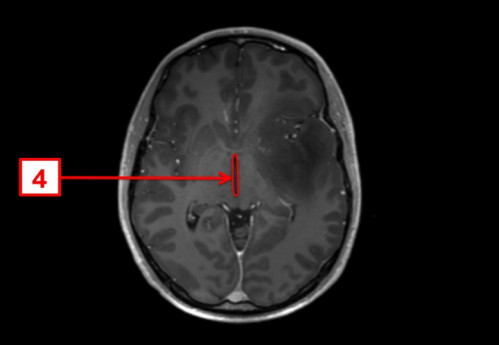

ICD: C71.9

ICD: R47.0

ICD: R51

23-jähriger Mann. Bereits seit Jahren plagen ihn Kopfschmerzen, die vor allem bei körperlicher Belastung auftreten. In den letzten Tagen fühlte er sich zunehmend unwohl, die Kopfschmerzen sind nun auch in Ruhe vorhanden.

Seit gestern Abend erbricht er sich mehrmals, und spricht, als ob er betrunken wäre.